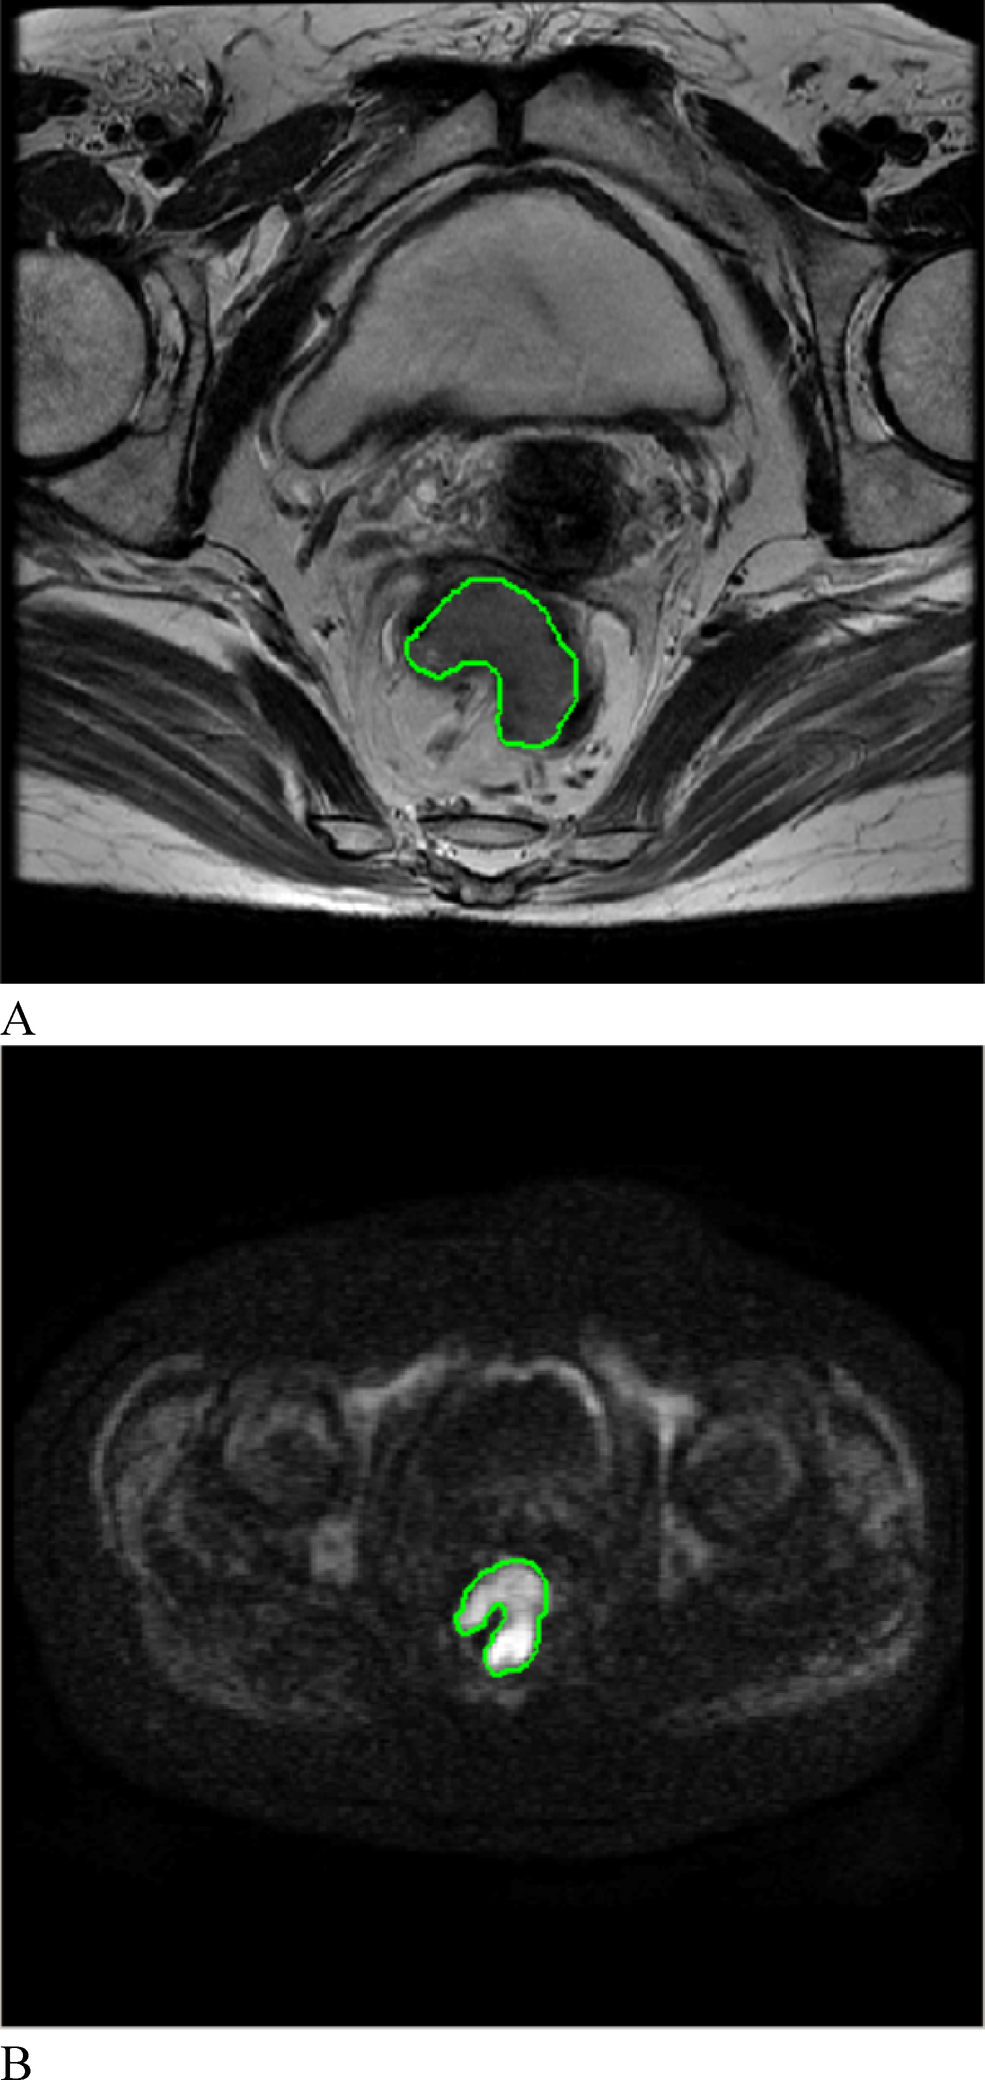

Fig. 2

From: Prediction of colorectal cancer liver metastasis through an MRI radiomic model

On oblique axial T2WI and DWI, the ROI was manually delineated layer by layer along the edge of the rectal cancer lesion. (A) T2-weighted imaging; (B) diffusion-weighted imaging.